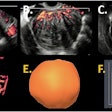

Conceptually, I think it is possible to define the term “radiological illustration” as an emerging discipline that transforms medical imaging data into an aesthetic and didactic narrative. I emphasize that with the motto “pixel by pixel handmade.” I am trying to open a “new path” for the use of visual communication in medical education by trying to combine scientific accuracy in radiological terms with artistic creativity. With this statement, I am trying to express that instead of modifying radiological images, I draw each pixel by hand using technological tools and create a new visual that is both artistically and scientifically original, while remaining faithful to radiological principles.

It’s important to note that radiological illustration should not be confused with medical illustration. The former has yet to be systematically defined in the literature. I believe it deserves recognition as a distinct sub-branch within the broader medical illustration domain.

In September 2025, I had the honor of exhibiting 35 selected illustrations at an international neuroradiology congress in Istanbul, jointly organized by the European Society of Neuroradiology, the American Society of Neuroradiology, and the Turkish Society of Neuroradiology. There were over 1,500 attendees. For the first time, my illustrations were displayed as true works of art under gallery lights and among a crowd. It was an unforgettable experience that left me with deep emotional memories.